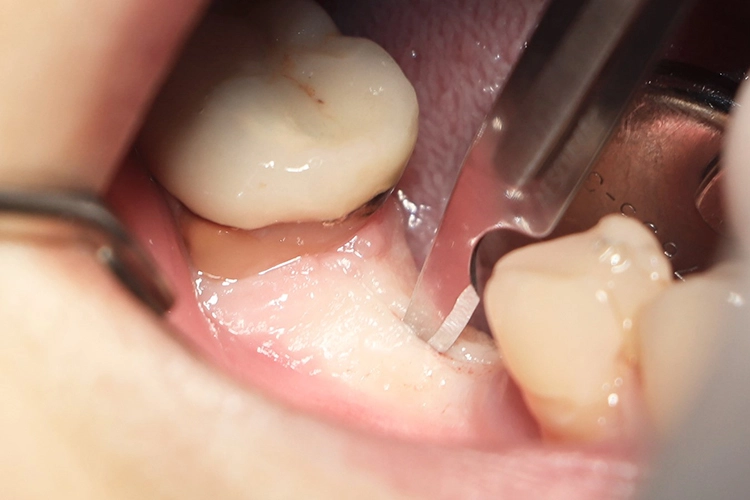

Im nächsten Schritt erfolgte die vollständig navigierte Implantation des Microcone-Implantates (Ø 5,0 mm, 9 mm Länge) in der Region 46 (Abb. 8-14) nach dem vom Hersteller empfohlenen Bohrprotokoll, das sich nach Knochenqualität und Implantatdurchmesser richtet. Die Chirurgie-Kassette (Abb. 6) ist übersichtlich aufgebaut und intuitiv zu bedienen. Zur schonenden Präparation des knöchernen Implantatbetts stehen je nach Implantatdurchmesser und Knochenqualität bis zu fünf verschiedene Bohrertypen mit Farbcodierung zur Verfügung. Das Implantat war für eine gedeckte Einheilung vorgesehen und der Kieferkamm wurde durch Nahtlegung speicheldicht verschlossen (Abb. 15).

Die Dokumentation des Implantatsitzes erfolgte mit einer postoperativen Panoramaschichtaufnahme (Abb. 16). Nach der gedeckten Einheilung erfolgte im Juni 2021 die geschlossene Implantatabformung mit Impregum. Abbildung 17 bis 25 zeigt den Ablauf von der Inzision drei Monate nach Implantation bis zum Einsetzen des Hybrid-Abutments mit Titan-Klebebasis und Zirkonaufbau bis zur finalen Zirkonkrone, die aufgrund einer Erkrankung der Patientin etwas später als vorgesehen im Juli 2021 eingegliedert werden konnte. Die Versorgung der insuffizienten Einzelkrone 47 erfolgt auf Patientenwunsch zu einem späteren Zeitpunkt.